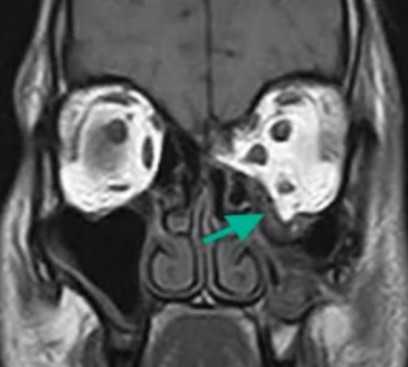

![Взрывной перелом орбиты на МРТ]()

Взрывной перелом орбиты на МРТ (изменения указаны стрелкой)